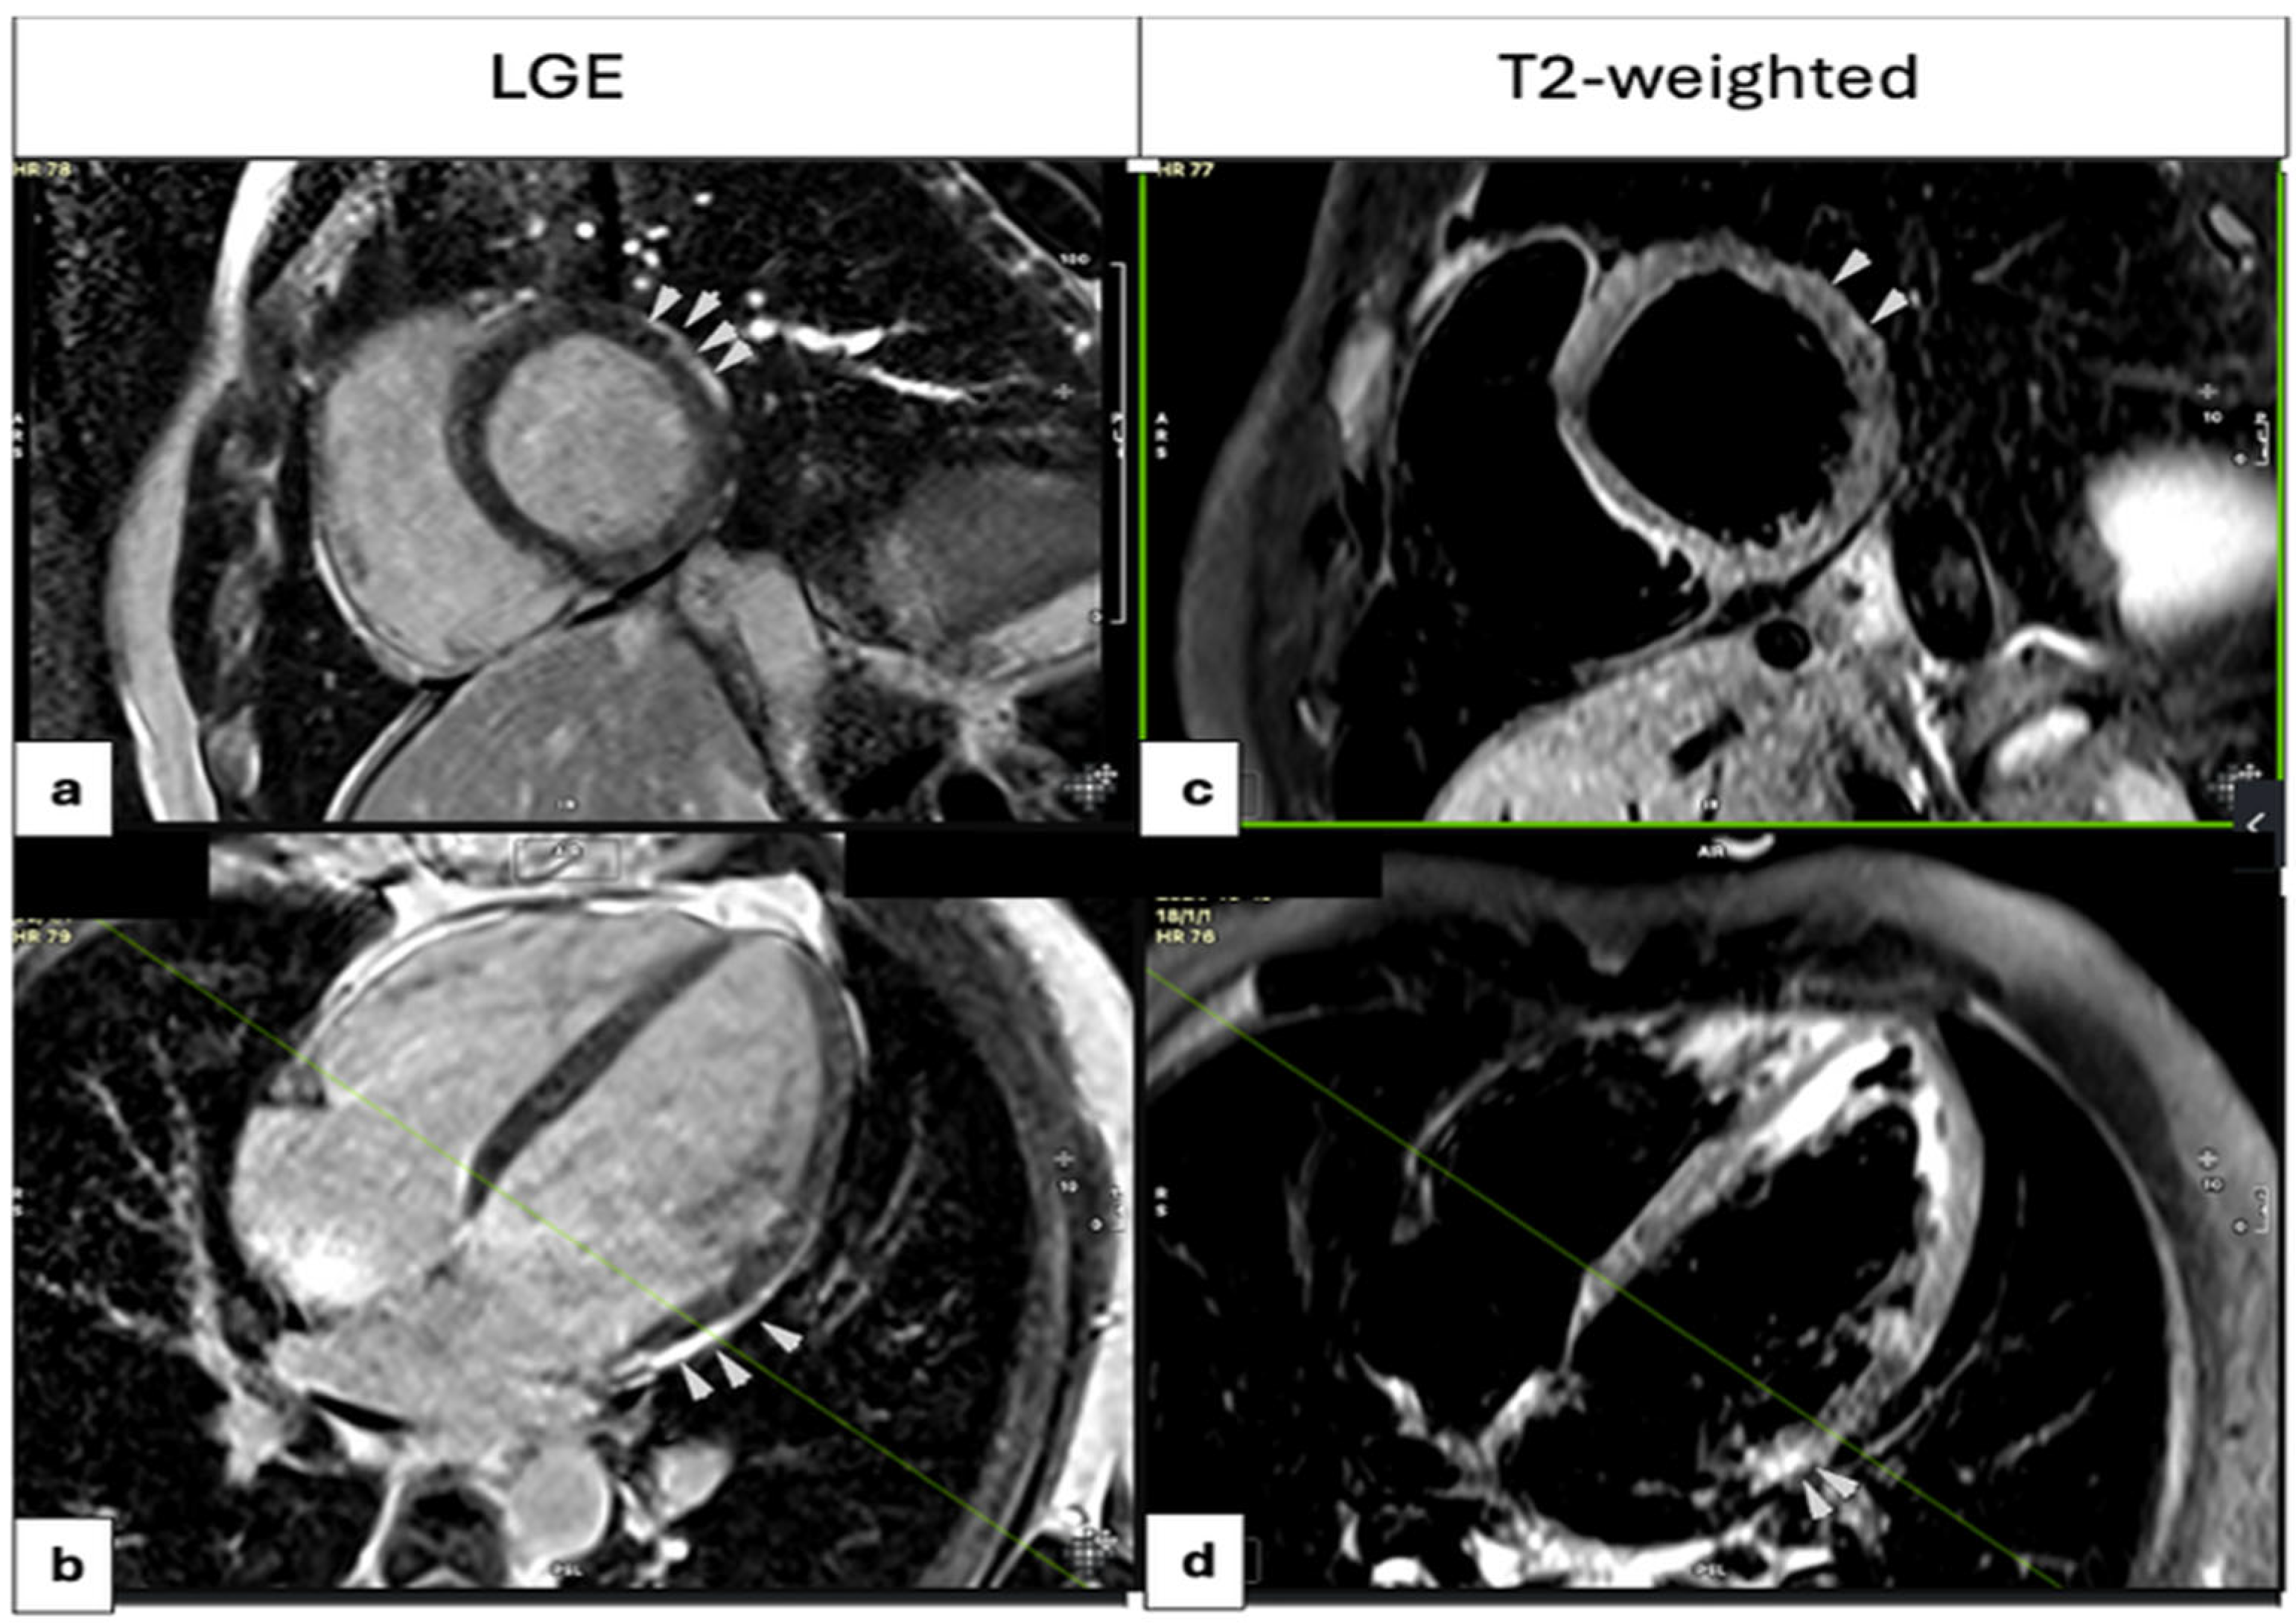

3.3.2. Imaging Modalities

3.3.4. Comparison Based on ECG Findings on Admission